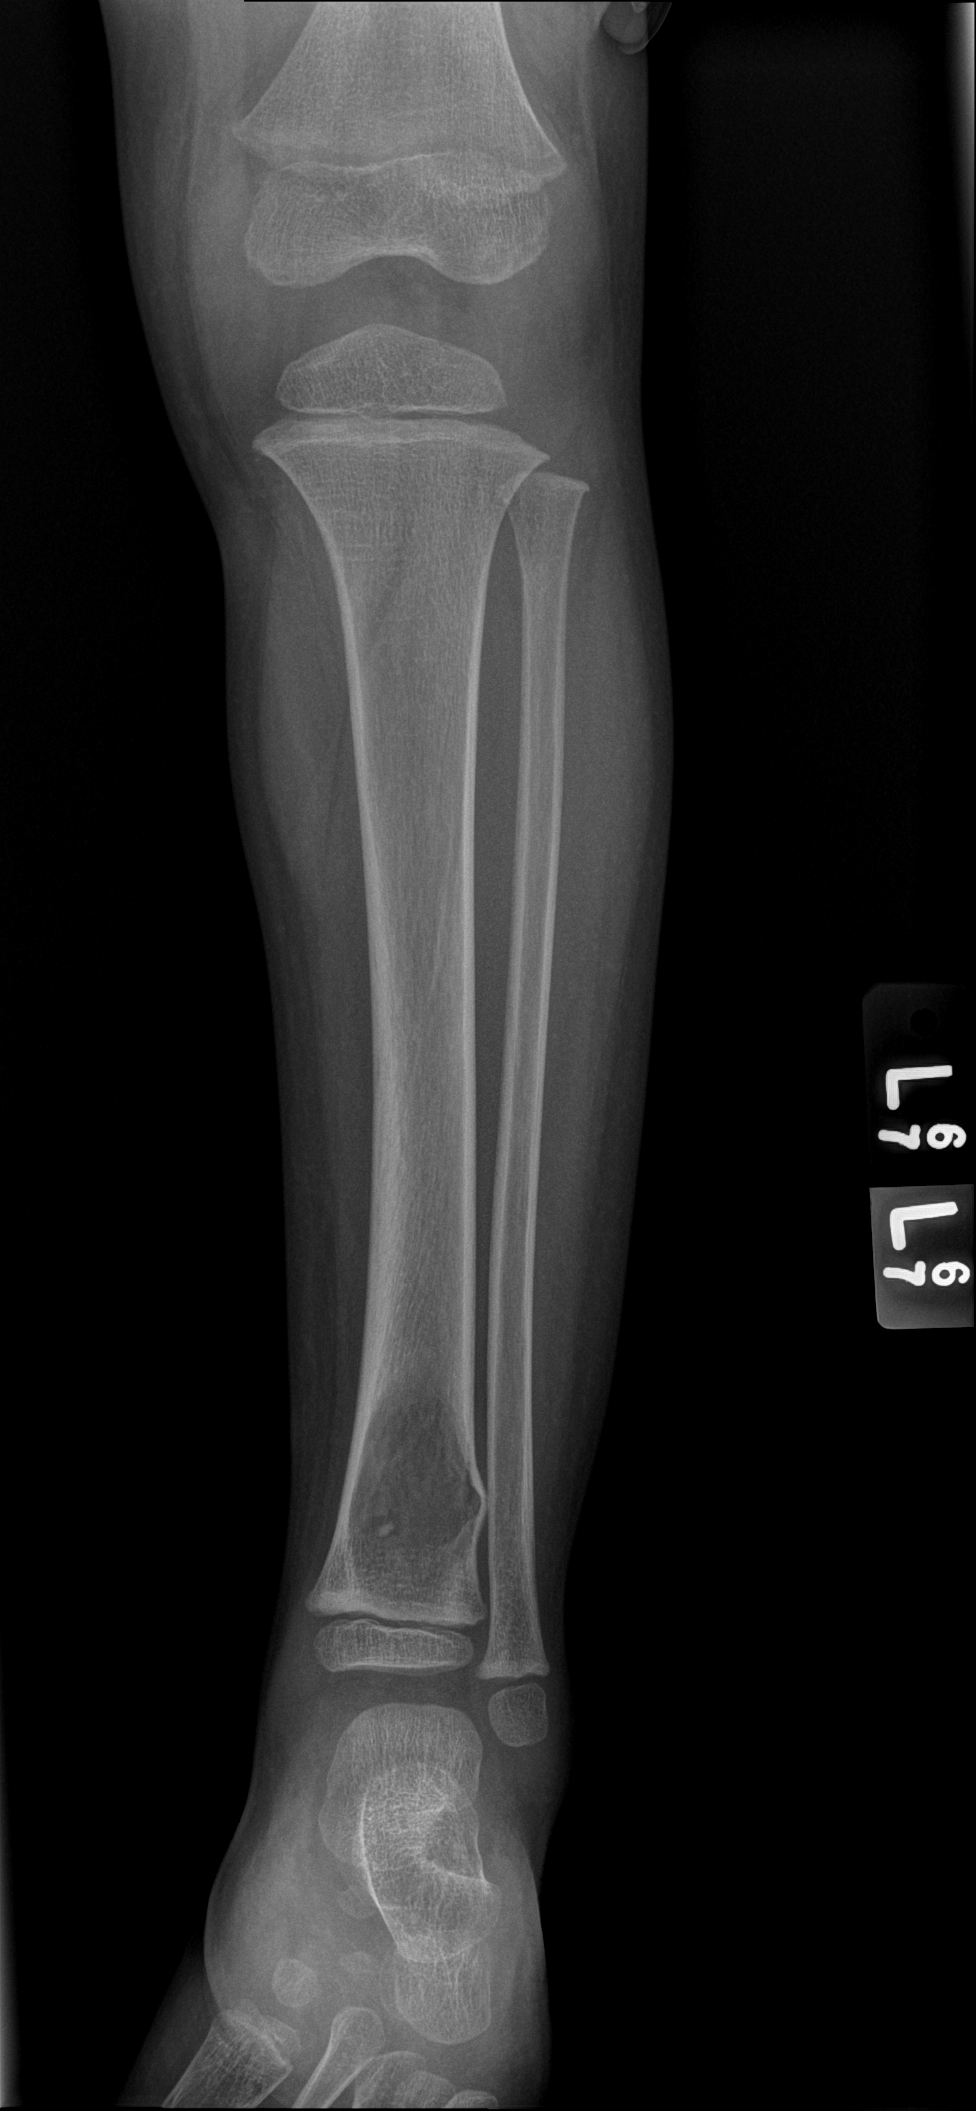

An x-ray and subsequent MRI were ordered of the ankle which demonstrated an expansile lytic lesion involving the metaphysis of the distal tibia measuring approximately 3.4 x 2.2 cm (Figure 1 and 2). The margins of this lesion are indistinct, and there is cortical irregularity at the anterior and lateral aspect of the distal metaphysis of the tibia, likely representing a pathologic fracture. The differential diagnosis includes infection, aneurysmal bone cyst, nonossifying fibroma, osteoblastoma and histiocytosis.

Figure 1. Xray of the distal tibia demonstrating the lesion.

Figure 2. MRI demonstrating the lytic lesion involving the metaphysis of the distal tibia.

In a study by Inyang et al, when PHE involved bone, imaging would demonstrate multiple to innumerable discontinuous tumors throughout the affected bone, involving the cortex and/or medullary cavity of the epiphysis, metaphysis, or diaphysis. On x-ray and computed tomography, the lesions appeared as well circumscribed, lobulated and lytic, with a sclerotic rim on some of the lesions. On magnetic resonance imaging, T1-weighted images would appear dark, and T2-weighted images would appear hyperintense.